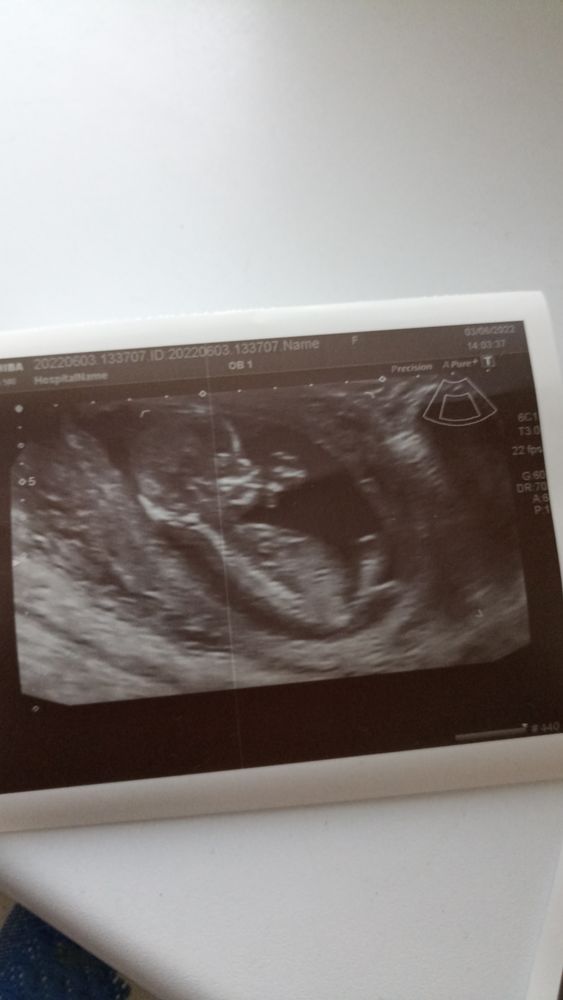

Алена Максимова в Клуб беременных 4 года Пол малыша ☺ Скрининг Девченки давайте повангуем на пол моего малыша ❤❤ у меня скоро УЗИ буду сверять потом ваши ответы. ❤❤❤ Посмотрите еще 20 записей на эту тему Отменить Ответить Половой бугорок Первый скрининг (узи) Чаты Беременных Выберите чат: Январята-2026 Февралята-2026 Мартята-2026 Апрелята-2026 Майчата-2026 Июнята-2026 Июлята-2026 Августята-2026